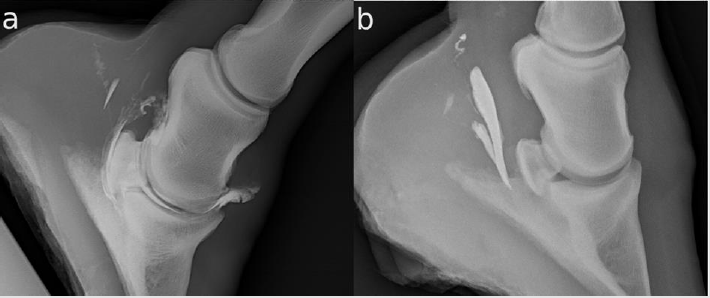

Twenty-three legs were injected. The NB was successfully injected only in 20/23 (86.96 %). In the other three legs, the CM was injected completely palmar to the DDFT (Figure 1b). The NB and the DIP were filled with CM in one horse (4.35 %) (Figure 1a). The DPr-PaDiO CE showed alliterations in 7/9 (77.78 %) legs with a clinical history of lameness. There was CM palmar to the DDFT (Figure 1a) and the NB was filled with CM in 5/20 (25.00 %) legs. The findings are summarized in Table 1. There were two DDFT lesions, one full flexor cortex lesion, three suspected ruptures of the NB and five NB adhesions.

Figure 1:

a. There is contrast medium (CM) in the navicular bursa and the distal interphalangeal joint, and some CM palmar to the deep

digital flexor tendon (DDFT)

b. The injection of the navicular bursa has failed. The CM is completely palmar to the DDFT.